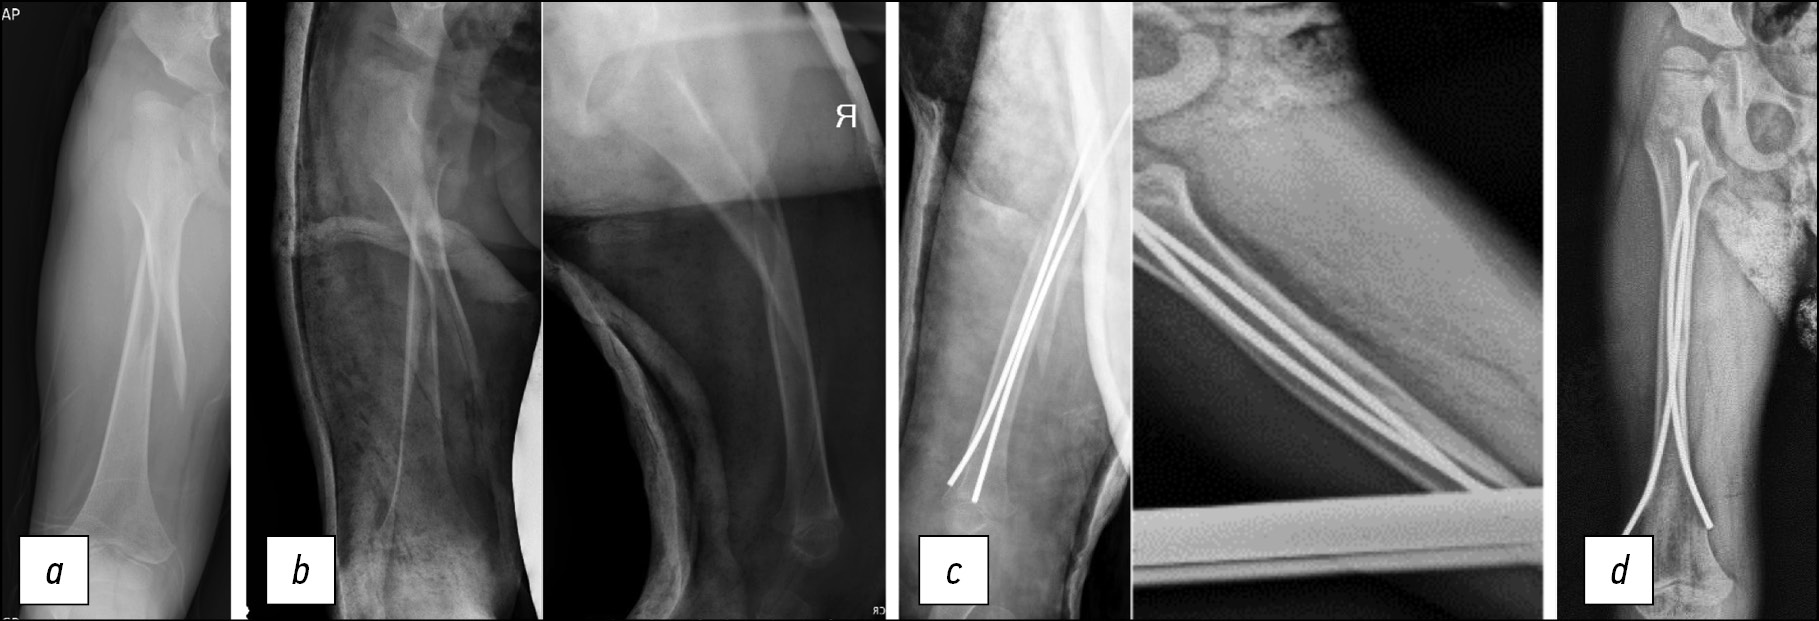

Ребёнок, 11 лет, ДЦП, IV уровень по GMFCS. Эпилепсии в анамнезе нет. Во время ЛФК произошёл перелом дистального отдела бедренной кости с выраженным угловым смещением. Учитывая высокие риски формирования сгибательной контрактуры, выполнено оперативное лечение: закрытая репозиция перелома, остеосинтез эластичными титановыми стержнями. Гипсовая иммобилизация на 3 недели с последующим удалением и началом разработки. Через 18 месяцев видны полная перестройка зоны перелома и сохранение оси конечности (рис. 3).

Рис. 3. Пациент А., 11 лет. Закрытый надмыщелковый перелом бедренной кости, рентгенограммы бедра: a — перелом; b — 4 недели после операции, стержни введены антеградно до дистального эпифиза; c — через полтора года после операции: видно возобновление роста кости, ремоделирование костной мозоли

Fig. 3. Patient A., 11 years old. Closed supracondylar fracture of the femur, radiographs of the femur: a — fracture; b — 4 weeks after surgery, rods were inserted antegrade to the distal epiphysis; c — one and a half years after surgery: resumption of bone growth and callus remodeling are visible